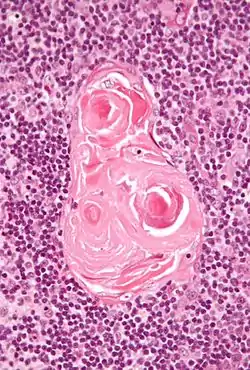

![]() Micrograph of a thymic corpuscle. H&E stain. | |

Hassall's corpuscles (or thymic corpuscles (bodies)) are structures found in the medulla of the human thymus, formed from eosinophilic type VI epithelial reticular cells arranged concentrically. These concentric corpuscles are composed of a central mass, consisting of one or more granular cells, and of a capsule formed of epithelioid cells. They vary in size with diameters from 20 to more than 100μm, and tend to grow larger with age.[1] They can be spherical or ovoid and their epithelial cells contain keratohyalin and bundles of cytoplasmic fibres.[2] Later studies indicate that Hassall's corpuscles differentiate from medullary thymic epithelial cells after they lose autoimmune regulator (AIRE) expression.[3] This makes them an example of Thymic mimetic cells.[4] They are named for Arthur Hill Hassall, who discovered them in 1846.[5][6]